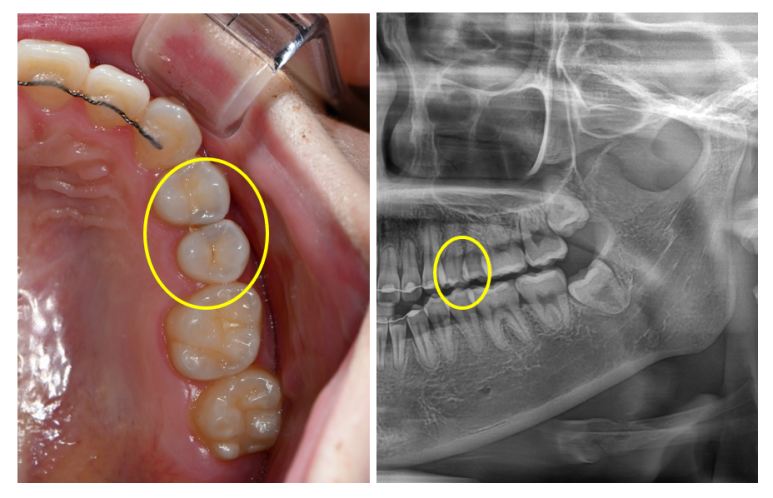

알아보기 쉽게 충치가 있는 곳만 떼서 표시를 해봤습니다.

옆면 충치가 생기셔서 검게 멍든 것처럼 보이는 치아... 양쪽이 동시에 썩었더라구요...

치과용 파노라마 사진을 보시면, 아주 잘~~~보시면 까맣게 동그라미진 곳이 보이실거에요.

어쨌든 옆면 충치를 발견했기에, 3M 에서 나온 Lava Ultimate라는 비싼 재료의 레진인레이 치료 계획을 세웠습니다.

비교적 앞쪽의 치아이기 때문에, 크게 웃으면 보일수도 있어서 치아색의 인레이로 결정했습니다!